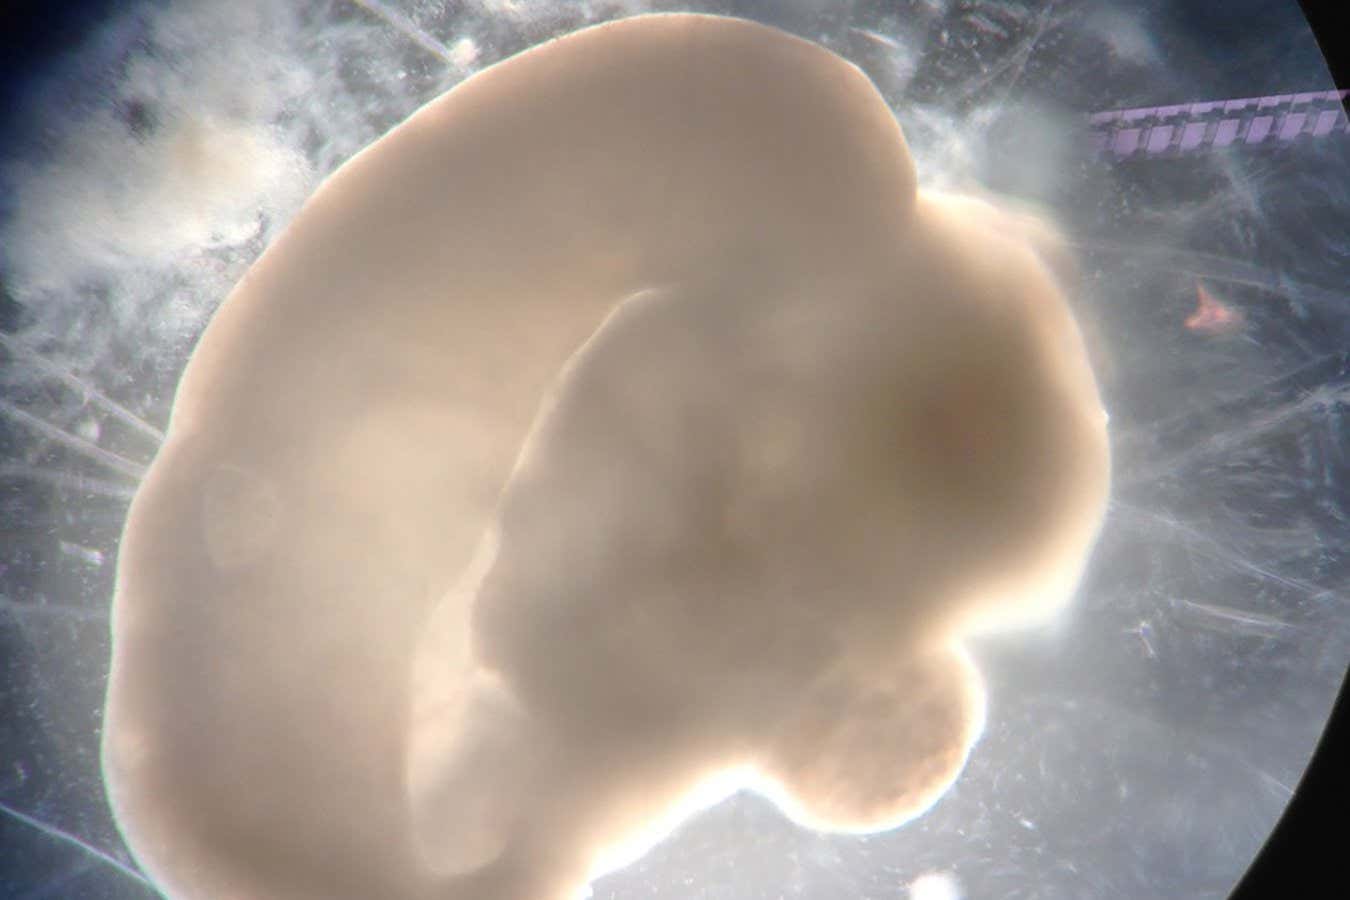

A 100-day-old brain organoid

Madeline Lancaster

Since Madeline Lancaster first created brain organoids back in 2013, they have become widely used for brain research around the world. But what exactly are they? Are they effectively miniature brains in dishes? Could implanting them in animals create super-smart mice? How close are we to crossing ethical lines? Michael Le Page visited Lancaster at her lab at the MRC Laboratory of Molecular Biology in Cambridge, UK, to find out.